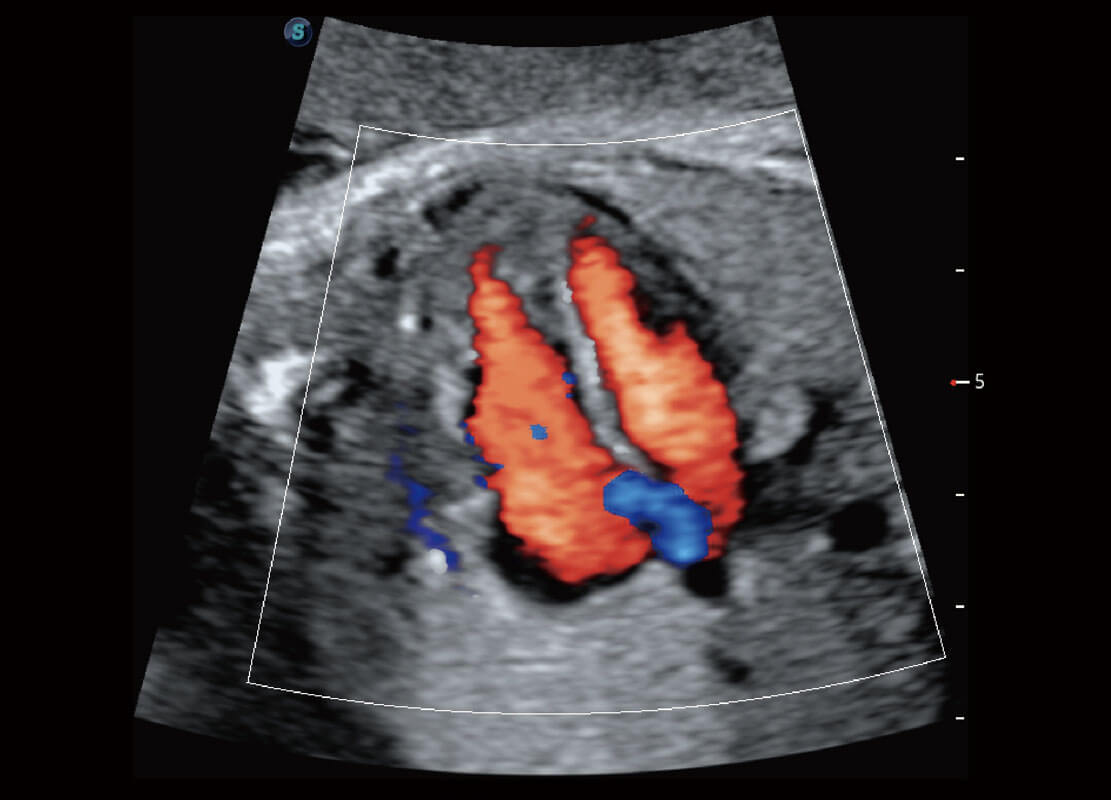

生殖健康

P60优异的图像质量搭载专科探头,在妇科基础疾病的诊断、卵泡生长的监测、输卵管通畅情况的判别等方面为您提供生殖应用方案。

• 腔内妇科-宫腔分离

• 腔内妇科-卵巢

• 腔内三维-宫内节育器

• 腔内三维-光影成像